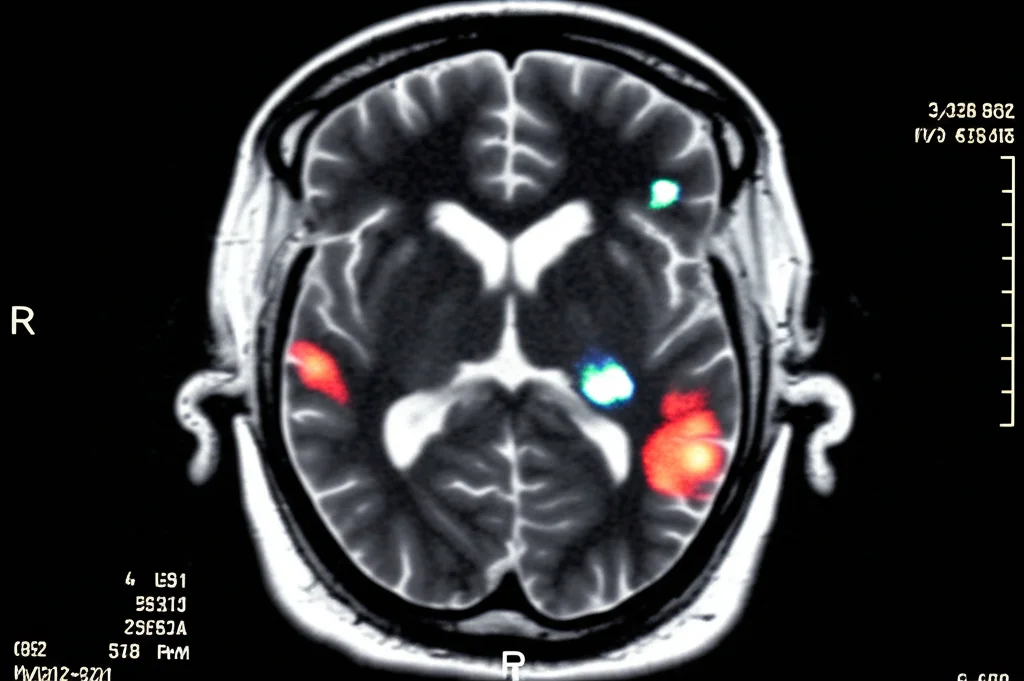

Per vedere meglio, si procede con una Risonanza Magnetica (RM) cerebrale. E qui le cose si fanno ancora più strane. La RM conferma le lesioni, ma ne mostra anche altre, in particolare nei talami, due strutture profonde e centrali del cervello, su entrambi i lati (bilaterali). Queste aree mostrano una “restrizione della diffusione” (iperintense in DWI, ipointense in ADC), un segno tipico dell’ictus ischemico molto recente. Ci sono anche segni di piccoli sanguinamenti passati (depositi di emosiderina, visibili in SWI). La diagnosi sembra puntare verso un infarto nell’area dell’arteria cerebrale anteriore e forse dell’arteria di Percheron, un vaso che irrora proprio i talami.

Ma come la mettiamo con quelle lesioni cerebrali che sembravano un ictus? Qui sta il punto affascinante e la sfida diagnostica. Le lesioni bilaterali nel talamo con restrizione della diffusione sono state descritte in altri rari casi di Dengue, ma la loro interpretazione è dibattuta. Sono veri infarti ischemici o sono qualcos’altro?

Nel nostro paziente, una RM di controllo eseguita 4 giorni dopo la prima mostrava che le lesioni erano ancora lì, con segnali simili. In un vero ictus ischemico, ci aspetteremmo una certa evoluzione, una “normalizzazione” del segnale DWI dopo alcuni giorni. Il fatto che ciò non sia avvenuto suggerisce un meccanismo diverso. Studi post-mortem su pazienti con quadri simili hanno mostrato aree di edema marcato (gonfiore), capillari dilatati e congesti, ed emorragie, piuttosto che aree di tessuto morto per mancanza di sangue (infarto ischemico classico).

Inoltre, le lesioni da Dengue spesso sono simmetriche e bilaterali, non sempre rispettano perfettamente i territori vascolari, e presentano frequentemente microemorragie (visibili in SWI), molto più di quanto si veda negli infarti classici. Quindi, quelle lesioni che inizialmente urlavano “ictus”, erano in realtà una manifestazione dell’encefalite da Dengue, probabilmente dovuta a infiammazione ed edema causati dal virus o dalla risposta immunitaria.